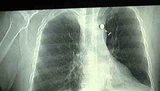

Het ziekenhuis Adao Pedreira Nunes in Brazilië is synoniem geworden voor eerste hulp bij schotwonden. In de wijk waar het staat is veel bendegeweld en er worden dagelijks bendeleden en onschuldige voorbijgangers naar de eerste hulp gebracht. Wesley liep een dag mee in dit ziekenhuis dat iedere maand zo'n 140 patiënten met kogels in hun lijf behandelt.